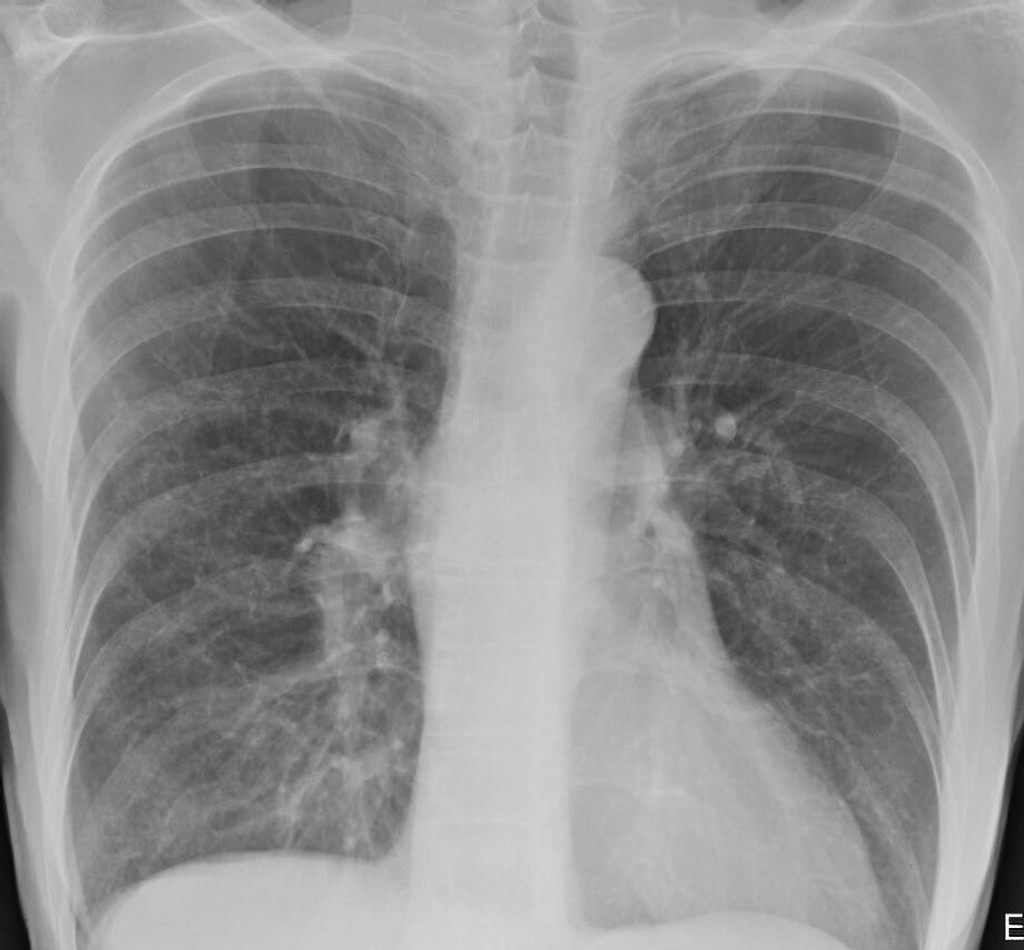

Na röntgenových snímkach sú pľúca po ťažkom priebehu ochorenia COVID-19 silno poškodené aj s jazvami.

Doktorka Brittany Bankhead-Kendallová ošetrovala už tisícky pacientov s koronavírusom. Podľa jej zistení sú röntgenové snímky pľúc fajčiarov trocha zahmlené, ale tie po-covidové sú úplne biele, vykazujú značné zjazvenie a nedostatok vzduchu vstupujúceho do orgánov.

„Po-covidové pľúca sú oveľa zničenejšie, ako akýkoľvek snímok pľúc tuhých fajčiarov, aké som kedy videla," prezradila na Twitteri. „A dýchavičnosť pretrváva a môže sa to zhoršiť," dodala.

Keď sa vzduchové vaky naplnia tekutinou, nie sú schopné prijať toľko kyslíka, ako telo potrebuje. Začína sa to príznakmi ako kašeľ a dýchavičnosť. Na röntgenovej snímke potom pľúcne tkanivo zasiahnuté koronavírusom vyzerá ako z mliečneho skla. Dôsledkom je situácia, keď cez postihnuté tkanivo neprejde kyslík a nenadviaže sa v krvi na hemoglobín. Tým klesá zásobenie tkanív a orgánov tela kyslíkom a človek zomiera.